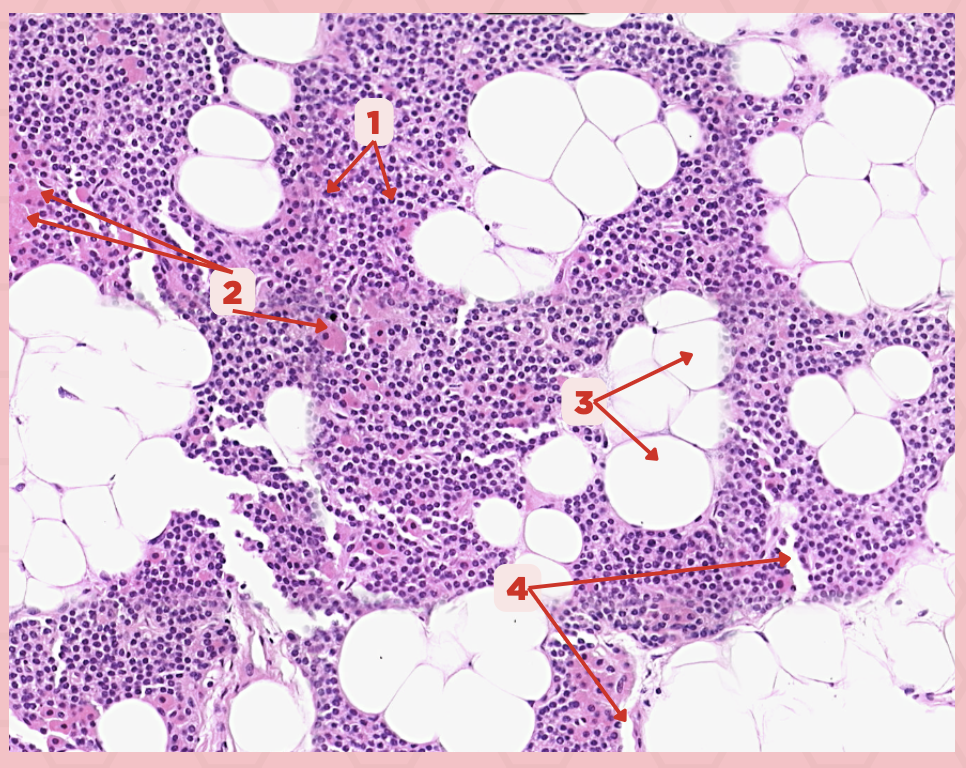

Parathyroid

Identify the specimen.

Chief Cells

Identify the specimen labeled as 1.

Oxyphil Cells

Identify the specimen labeled as 2.

Adipocytes

Identify the specimen labeled as 3.

Capillaries

Identify the specimen labeled as 4.

Newborns

Pointer #2 is hardly present in the parathyroid glands of _____.

Parathyroid

Identify the specimen.